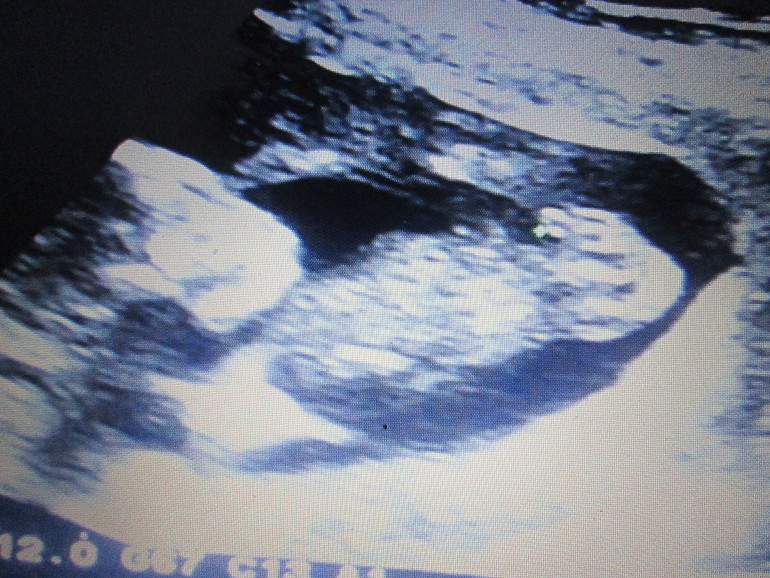

Сегодня с мужем ходили делали УЗИ-определение пола. У нас будет СЫН!!!

Все замечательно, плацента так и по передней стенке, высоко!!!

Вот фото нашего сыночка, справа видно наше приданное :)